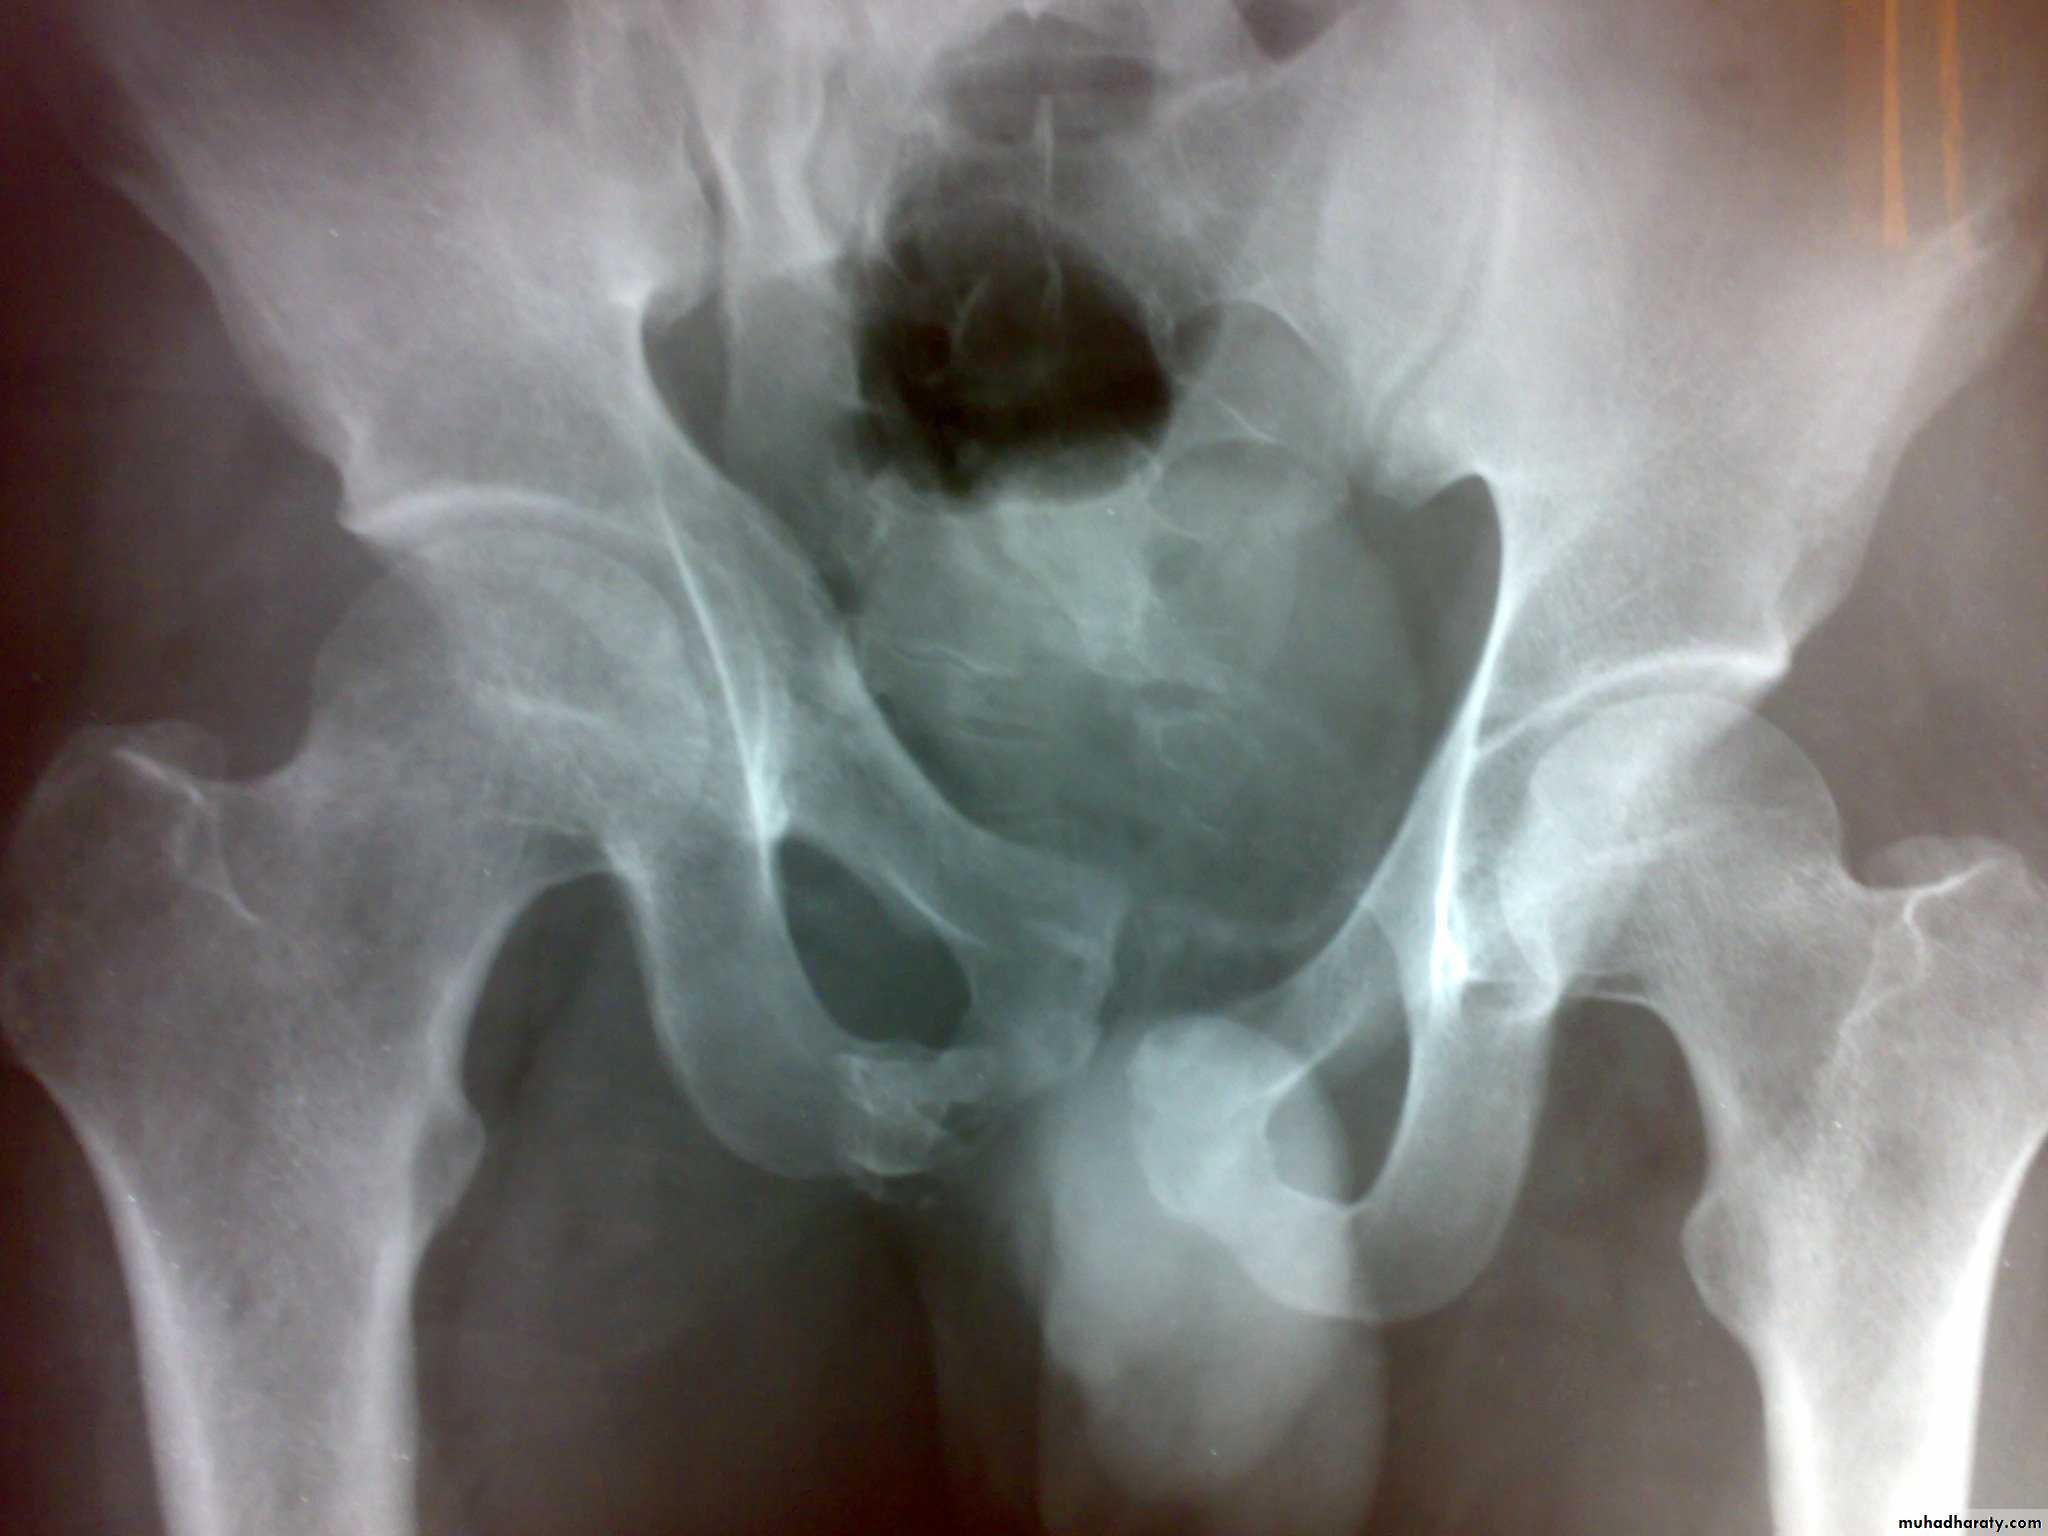

Types of unstable fracture pelvic ring

1- antero-posterior compression (open book).

2- lateral compression (closed book).

3- Vertical force cause vertical displacement of the innominate bone on the same side.

4- combination injuries.

X- ray: Ideally five views should be obtained : Standard anteroposterior view, inlet view, outlet view, right oblique view, and left oblique view, but x-ray shouldn't be done until the patient become stable .